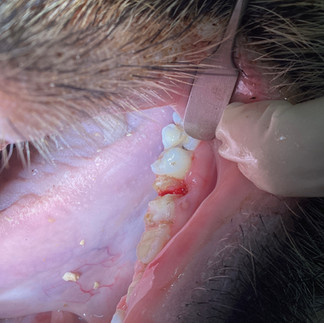

症例:マイクロブタ、4歳、去勢♂、24kg

この症例は、全身麻酔下で過長になった犬歯のカットとスケーリングを行った際に偶然、歯冠歯根共に複数箇所破折が認められました。

おそらく日常的な歯ぎしりが原因と思われます。

後日、歯科専門獣医師と共に抜歯処置を行いました。

この症例では露髄していた2箇所の歯の抜歯処置を行いましたが、歯根が複数に粉砕されており、とても苦労しました。